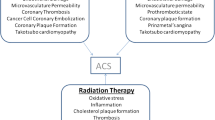

Certain chemotherapeutic agents have been well-established to cause accelerated coronary atherosclerosis and ACS. 5-Fluorouracil (5-FU) and its oral prodrug capecitabine are well-known to induce coronary vasospasm and precipitate ACS by activating protein kinase C and causing smooth muscle vasoconstriction [22,23,24,25,26]. Bevacizumab, a VEGF inhibitor, and tyrosine kinase inhibitors, such as sorafenib and sunitinib, are associated with an increased risk of arterial thrombosis [27,28,29,30]. Multiple cases of ACS secondary to rituximab, cisplatin, and taxols have been reported [31, 32]. Carfilzomib, a newly approved proteasome inhibitor used in the treatment of multiple myeloma, has been associated with an increased risk of heart failure, ischemic heart disease, and hypertension [33]. Hormonal therapies for breast cancer have been shown to increase the risk of cardiovascular events [34]. Interestingly, even patients who undergo hematopoietic stem cell transplants are at risk for cardiovascular toxicity, including CAD [35]. Immune checkpoint inhibitor (ICI) therapy-related cardiomyopathy and myocarditis have been well-established [36]. Recent data suggest a 3.3-fold increased risk for atherosclerotic cardiovascular events at 2 years after ICI therapy [37], although a direct causal mechanism is still under investigation. In a sub-analysis of that study, comparing atherosclerotic plaque volume in aortas using computed tomography (CT), an increase in plaque volume was noted with ICI therapy [37]. Interestingly, the concomitant use of statin and steroids had a moderating effect, showing the importance of optimizing cardiovascular risk factors during ICI therapy [37]. In a cohort study of nearly 700 patients, Laenens et al. found a 10% incidence of heart failure, ACS, and stroke in cancer patients within 1 year of initiating ICI therapy, almost double than those not on ICI therapy [38•].

Ionizing radiation affects both cancerous and non-cancerous cells, especially the rapidly proliferating endothelial and bone marrow cells. The pathogenesis of radiation-induced vascular disease starts with oxidative stress, ROS formation, endothelial inflammation, and dysfunction with increased vascular permeability, finally leading to damage to the vasa vasorum [39]. Chest radiotherapy can accelerate the progression of pre-existing CAD. The typical pattern of radiation-induced coronary artery disease (RICAD) is ostial stenosis with severe left main disease, along with ostial right coronary artery and left anterior descending artery stenoses. RI-CAD with ostial and multivessel stenosis is usually seen after extensive mantle radiation in Hodgkin’s lymphoma, breast cancer, and esophageal cancer [40]. While majority get standard of care treatment, patients with refractory to treatment, radiation-induced heart disease have been reported [41].